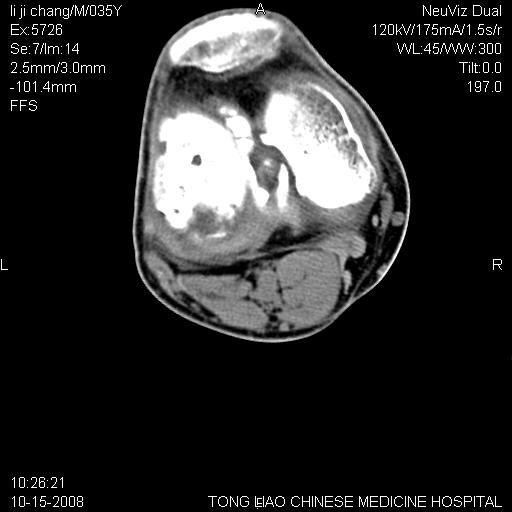

男,35岁,骨科诊断骨性关节炎。继往使用过激素,现股骨头坏死。膝关节病变,请会诊

一元论-----亦考虑为坏死

支持考虑无菌坏死

支持无菌坏死伴退行性骨关节病.

剥脱性骨软骨炎:是一种关节下软骨及软骨下骨缺血性坏死。

支持 无菌性坏死伴退行性骨关节病。